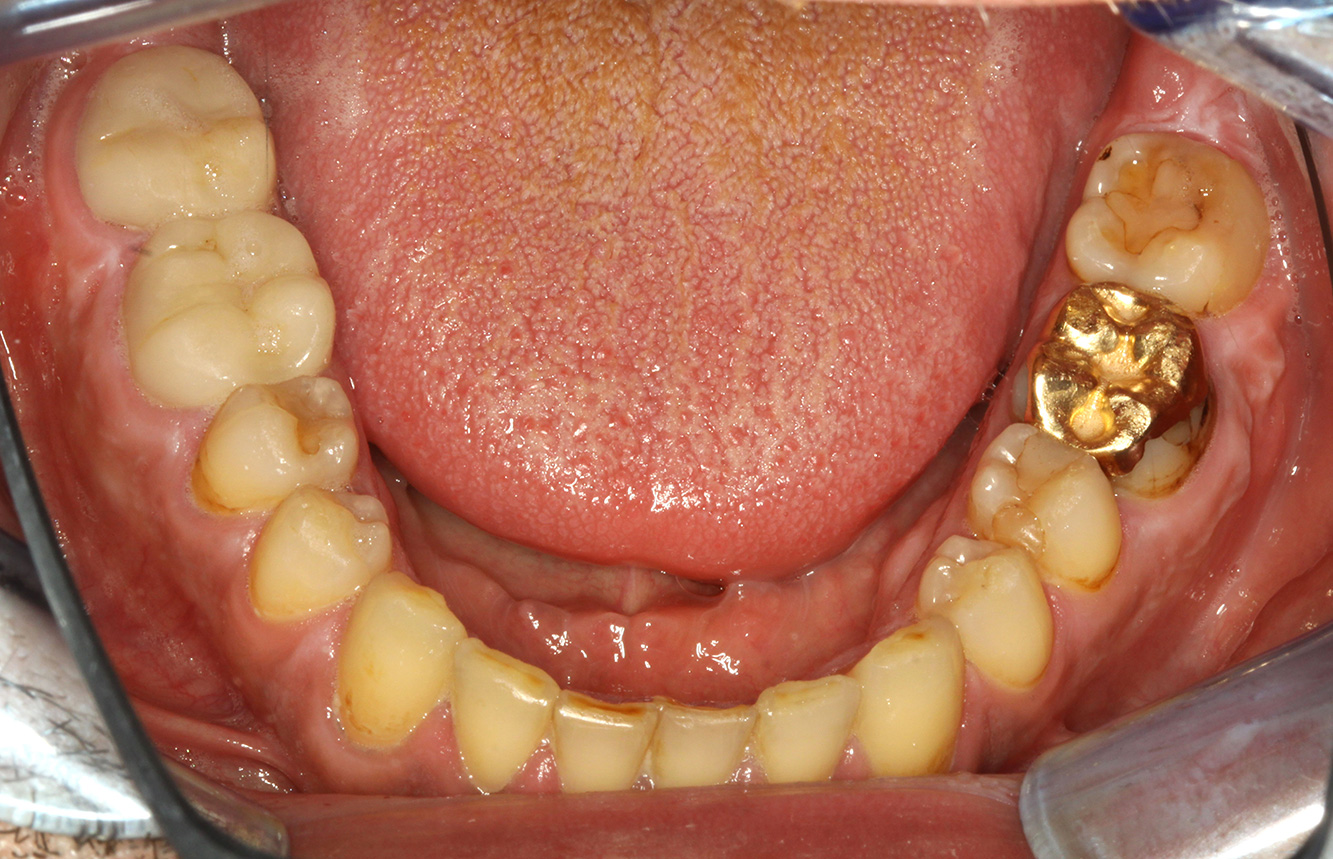

The transplant patient with gingival overgrowths

A 71-year old patient presents with having previously undergone a kidney transplant and with a history of hypertonia (high blood pressure). Due to his medical history, long-term medication with cyclosporine is required to suppress the immune system, as well as amlodipine to lower blood pressure. The patient also reports sensitive and bleeding gums. From an oral health perspective, the patient has undergone dental restoration and has eight missing teeth, pronounced gingival growth, and grade B, stage II periodontitis with active pockets and initial root caries on tooth 22. The caries risk assessment determines a moderate risk of caries (API 60). The following treatment recommendations can be determined for the prophylaxis session. more